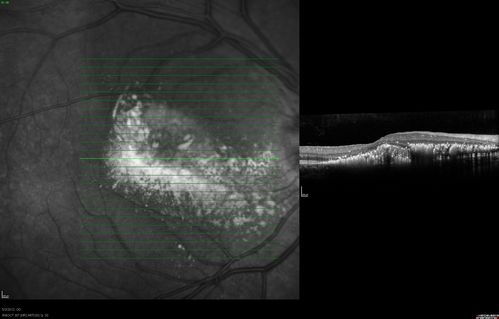

| Filename: | 7__oct_com_od.jpg |

| Album name: | / Coats disease |

| Attribution (if wanted) enter name or institution here: : | saunders/pavan/usf eye institute |